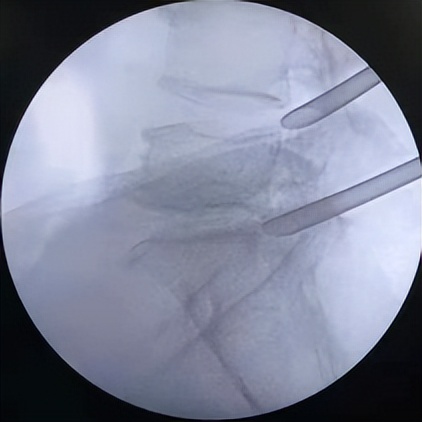

微创椎间孔镜术中